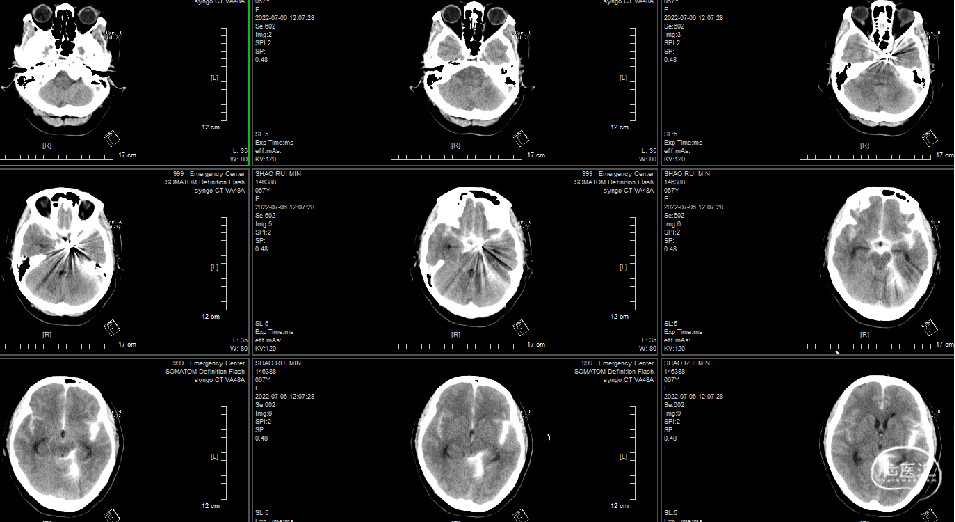

头颅CT(平扫)、胸部CT(平扫)第一次:

1、自发蛛网膜下腔出血,建议CTA检查。

急诊头颅CT:自发蛛网膜下腔出血。